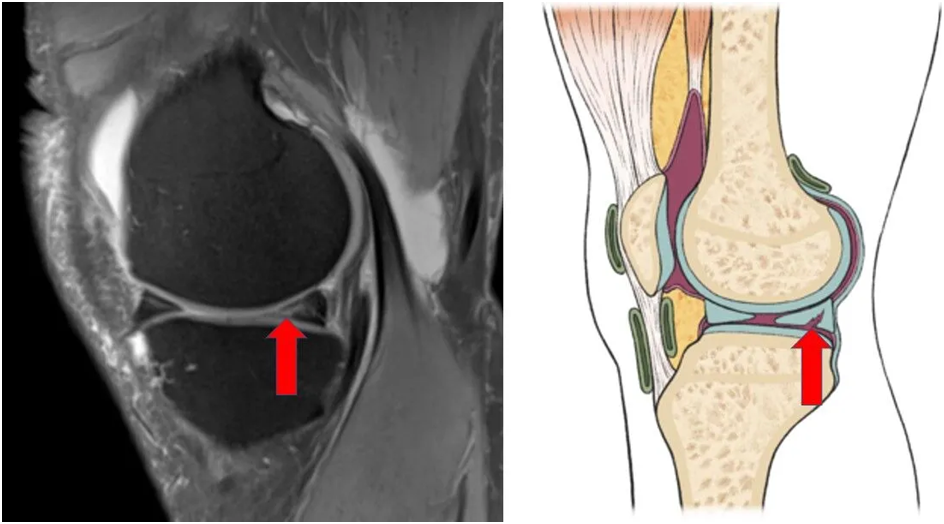

A meniscus tear is a common knee injury that occurs when the meniscus, a C-shaped cartilage in the knee, gets torn due to sudden twisting or heavy impact. The meniscus acts as a cushion between the thigh bone (femur) and shin bone (tibia), helping in smooth movement and shock absorption.